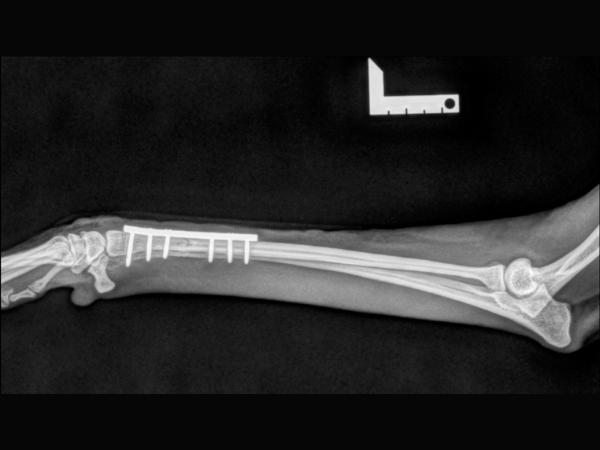

<術後のレントゲン>

インプラントによる内固定と海綿骨移植を行いました。

▼術後